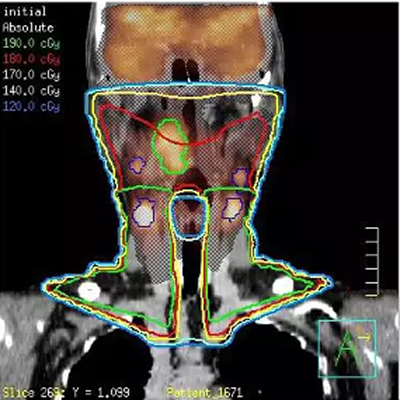

在您进行轮廓勾画以及使用多模图像配准进行 Pinnacle³ 整合治疗计划时,Syntegra能为您带来更强的信心。Syntegra 的多模配准软件能够缩短放射治疗周期,并取得更准确的诊断结果。

Syntegra 能够将生理学影像(如 PET 等)与解剖学影像(如 CT 或 MR)进行自动匹配,使临床医生无需手动调整匹配的影像。

作为飞利浦 Pinnacle³ 放射治疗计划系统的一部分,Syntegra 能够帮助您弥合诊断与治疗之间的鸿沟。例如,放射肿瘤科医生可以将 PET/CT 肿瘤轮廓输入 Pinnacle³ 治疗计划并对其进行回顾,并且可以使用放射科医师已经确定的影像和感兴趣区域。Syntegra 已被归为飞利浦 AcQSim³ CT 模拟软件的一个组成部分。